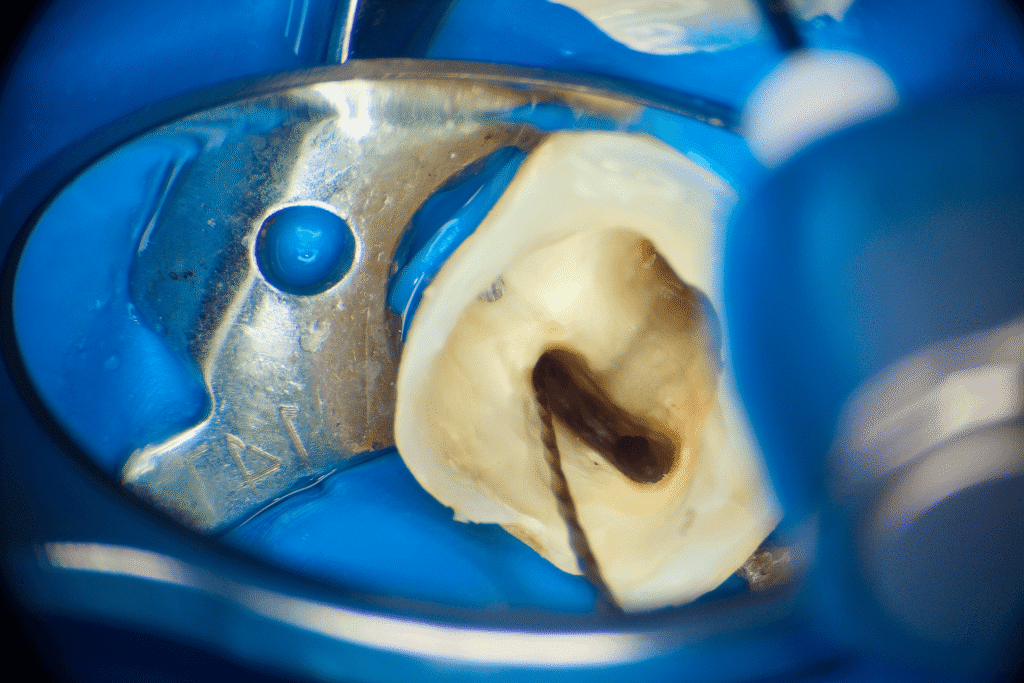

Pacjentka lat 54 trafiła do mojej kliniki skierowana z innego gabinetu celem leczenia endodontycznego zęba 46. W badaniu stwierdziłem znaczny zanik światła kanału korzeniowego. W badaniu tomograficznym stwierdziłem całkowity zanik kanału korzeniowego w strefie mezjalnej. Korzeń dystalny mimo widocznego światła kanału na CBCT, widoczne było wiele zwapnień w środkowej części kanału. Po wykonaniu dostępu endodontycznego zlokalizowałem materiał wypełniający kanał pozostawiony po poprzednim nieskutecznym leczeniu endodontycznym. Do usunięcia wykorzystałem laser 2780nm (25mJ/puls). W kolejnych etapach instrumentacji wspomaganie ultradźwiękami oczyściłem strefy mezjalną i dystalną. Instrumentacja themo-

mechaniczna polegała na zastosowaniu protokołu ciągłej chelacji wraz z użyciem lasera

2780nm z końcówką płaską (50mJ/puls) celem udrożnienia przestrzeni endodontycznych. Po wstępnym uzyskaniu drożności zastosowałem instrumentację maszynową wspomagająco celem udrożnienia przestrzeni. Finalnie obturacja z zastosowaniem ćwieków gutaperkowych kalibrowanych na WL i uszczelniacza na bazie krzemianów wapnia. W przeciwieństwie do tradycyjnych uszczelniaczy, nie wymaga mieszania, co eliminuje błędy w proporcjach i zapewnia powtarzalną konsystencję. Jest materiałem wysoce biokompatybilnym i bioaktywnym. Finalnie zamknięto ząb odbudową kompozytową tymczasową i skierowano na dalsze leczenie protetyczne do gabinetu kierującego pacjenta.